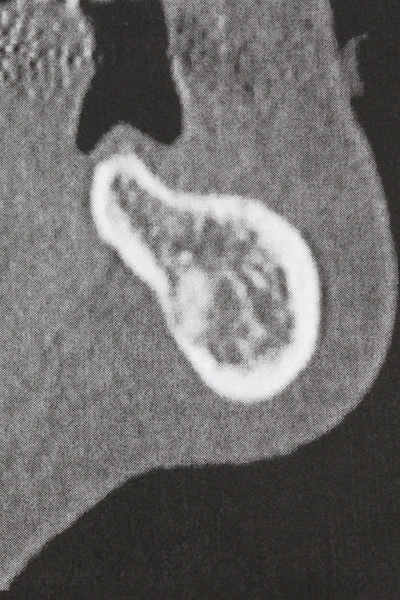

Quando le procedure chirurgiche vengono eseguite sull'osso nelle immediate vicinanze di strutture sensibili, come vasi sanguigni o nervi, gli strumenti rotanti pongono un rischio significativo di lesione iatrogena. I dispositivi piezoelettrici possono essere utili per la preparazione delle coperture ossee e la rimozione del tessuto duro in prossimità dei nervi, in particolare per la loro esposizione dopo una lesione iatrogena, ma anche durante la lateralizzazione dei nervi per le procedure di resezione e ricostruzione o il posizionamento di impianti (figg. 17-20). Il contatto leggero tra puntina piezoelettrica e nervo non causa generalmente danni, ma se si procede senza prestare attenzione con movimenti a sega o raccordi con residui di substrati ossei possono verificarsi danni al nervo temporanei o anche permanenti. Il rischio di danno, tuttavia, è considerato sostanzialmente inferiore al rischio presente utilizzando seghe o frese (Pereira, Gealh et al. 2014).